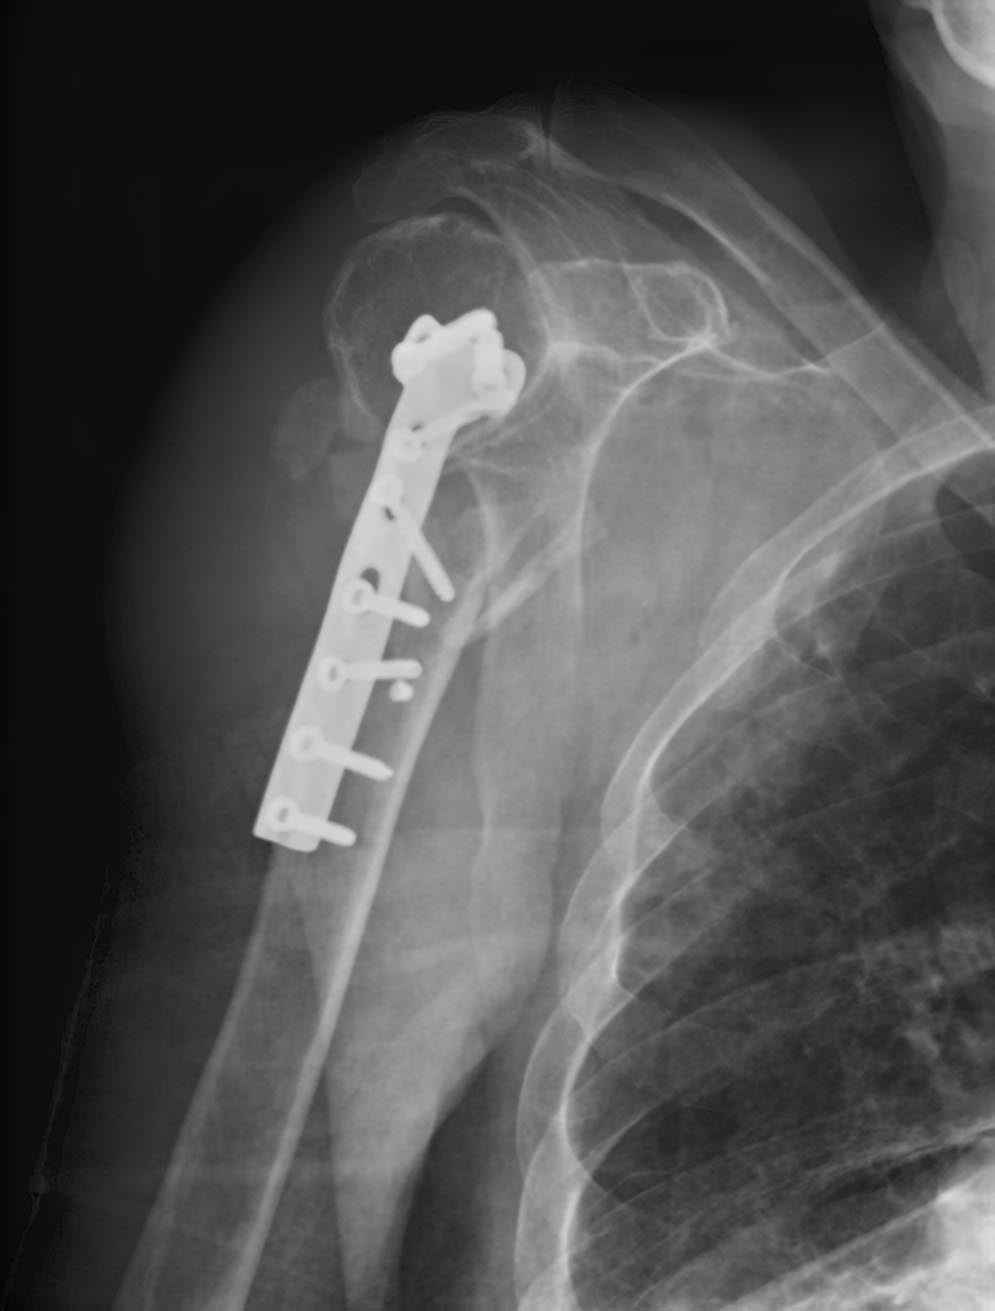

Перелом хирургической шейки плеча, 1947 г.р. Переведен из районной больницы, оперирован 3 дня назад Т-образной пластиной.

Что с этим делать сейчас? Со слов, оперирующего хирурга жуткий остеопороз (головка как скорлупа).

Тут и по одной проекции все понятно.

Надо делать ревизионный остеосинтез. Удалять пластину, и нормально уже переделать либо пластиной, либо проксимальным гвоздем. Гвоздем, наверно, даже проще. То, что "скорлупа" - это обычное дело, на то PHN и придуманы, прекрасно все работает.

Удалить металлоконструкцию и реостеосинтез проксимальным реконструктивным стержнем. Можно даже коротким.